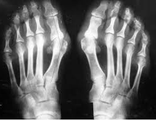

Деформации пальцев ног